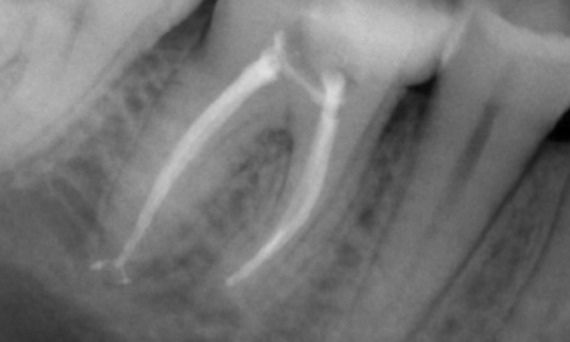

"Ich habe mich für TruNatomy entschieden, um so viel Dentin wie möglich zu erhalten, um die okklusale Belastung zu bewältigen und die Langlebigkeit des Zahns zu erhöhen." Dr. Abuelezz

Vorher: Bei der Untersuchung wurde eine Karies-Läsion am unteren rechten ersten Molaren festgestellt. Bei der röntgenologischen Untersuchung zeigte sich die Nähe der Läsion zum Pulpahorn. Zusammen mit den Hauptbeschwerden wurde die endgültige Diagnose einer chronischen irreversiblen Pulpitis gestellt.

Nachher: Die Zugangskavität wurde so konservativ wie möglich gestaltet. Da es sich um einen jungen Patienten handelte, war TruNatomy das System der Wahl. Wir mussten das Dentin so weit wie möglich erhalten, um die Fähigkeit des Zahns zur Bewältigung der okklusalen Belastung und die Langlebigkeit der endgültigen Restauration zu erhöhen.

Kairo, Ägypten